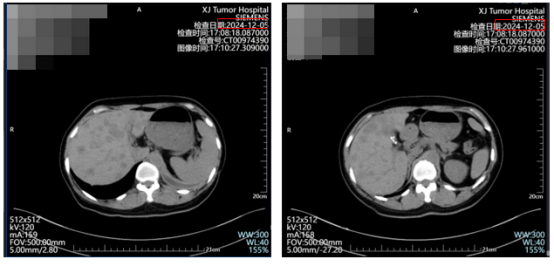

这次治疗方案调整为戈舍瑞林+瑞波西利+来曲唑+地舒单抗,我原本以为能稳住病情。可才过了三个月,肝脏和腰椎病灶不仅增多还变大,连原本稳定的肋骨也出现了新破坏。

图为:2024年12月肝脏新增多发病灶